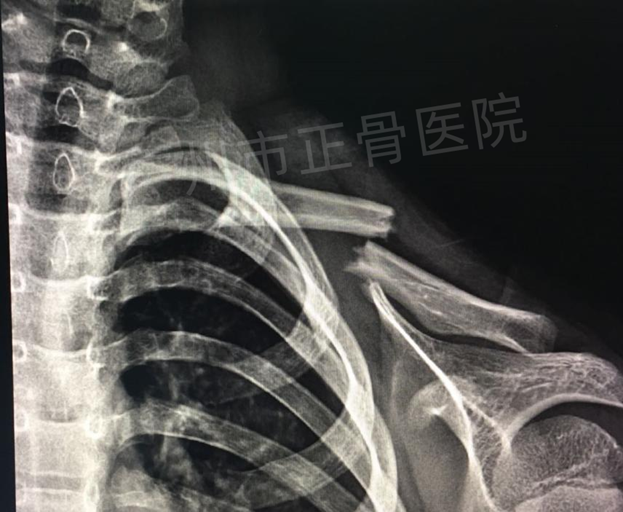

治疗:运用正骨手法复位后小夹板外固定治疗。复位后复查X线片提示骨折端对位对线明显改善。给予三角巾悬吊患肢,指导患者适当功能锻炼。4周后复查X线提示骨痂生长,骨折端稳定,予拆除夹板,检查患者肩关节活动正常。4个月后复查X线,骨性愈合。

▲复位后,骨折对位对线良好